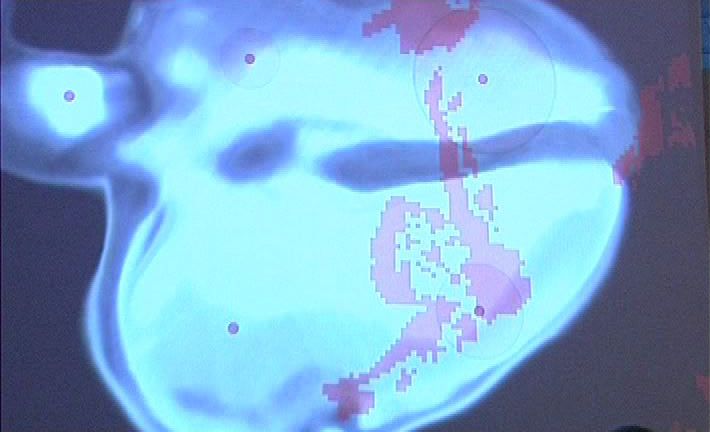

Dentro del espasio expositivo se instaló una superficie de proyecion de 4x5m en la cual se proyecta autentica imagen del corazón de la artista, realizada en cooperación con el equipo médico del hospital y el equipo técnico de rodaje.

El acercamiento del visitante a cierta área del mismo esquema inicia un concreto autentico sonido, que se produce en esa parte del órgano. Al mismo tiempo, la superficie de proyección muestra las figuras pixeladas de los participantes y su movimiento en partes del corazón proyectado. El visitante, como el receptor básico y a la vez el factor de cambio, al moverse dentro de la sección esquemática del corazón provoca cambios visuales y acústicos.